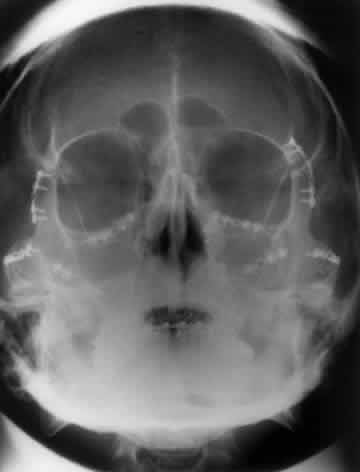

Foreign bodies of the eye or orbit can be detected with plain films. Although standard radiography should theoretically be able to visualize metallic fragments as small as 0.1 mm by 0.1 mm by 0.1 mm,30 a 1991 retrospective study reported lower actual sensitivities: In patients with a high clinical suspicion for an orbital or ocular foreign body, plain radiographs showed a 90% sensitivity for metallic foreign bodies, 71% sensitivity for glass, and lower sensitivities for wood and other materials. Metallic foreign bodies in the cornea showed a particularly high false-negative rate.30,31

The localization of foreign bodies with plain films is a recurring challenge. Echography and CT have diminished the need for plain film techniques for localization of foreign bodies, but the latter can be used when other imaging modalities are unavailable. Frontal and lateral projections are standard views in these studies (Fig. 18). Localization of a foreign body within the globe is possible with bone-free examination using dental film or by ocular rotation. This latter study localizes the foreign body to either the anterior or posterior segment of the eye. If the foreign body is anterior, the object will rotate in the same direction as the eye. The object will move in an opposite direction to eye movement if its location is in the posterior segment of the eye33 (Fig. 19). Pfeiffer34 and Worst35 used contact lenses as reference devices in localizing foreign bodies. These techniques are less commonly used.

Fig. 19. Foreign body localization using the ocular rotation technique. The patient is directed to look up, as in A, which shows the foreign body moving in the direction of upgaze. B. Foreign body is seen in an inferior location after the patient looked down. This foreign body was located in the anterior segment of the eye.